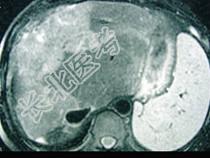

- 单项选择题女性,72岁, 腹胀不适1年,加重伴恶心、呕吐、乏力1个月, 影像检查如图,最可能的诊断为  (    )

- A、肝硬化腹水

- B、原发性肝癌

- C、肝血管瘤

- D、巴-希综合征

- E、局灶脂肪肝